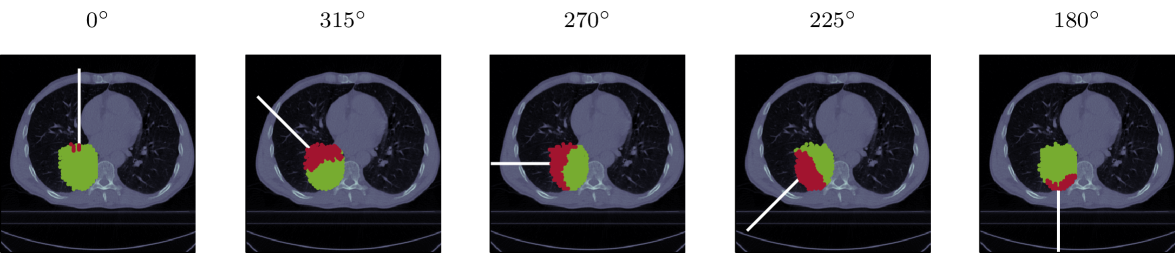

2.2 Investigated patient cases

We analyzed the residual helium range in lung cancer patient cases (hugo_data_2016), considering five different gantry angles: , as well as for tumors in the right lung or for tumors in the left lung. An example patient is shown in figure 2.

For the prostate and liver cases, we assigned a relative weighting factor of (equation 3), prioritizing more the number of detectable spots. For the lung cases, this weighting factor was set to . An overview of the investigated tumor sites and corresponding gantry angles is provided in figure 2.